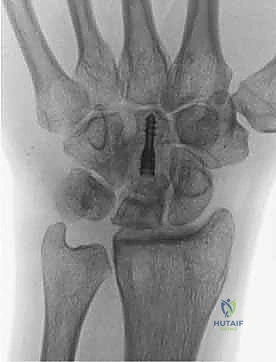

- الأشعة السينية (X-rays): هي الخطوة الأولى. في المراحل المبكرة جداً، قد تظهر الأشعة السينية طبيعية تماماً. في المراحل اللاحقة، يظهر العظم الهلالي بلون أبيض ناصع (متصلب)، ثم يبدأ في الظهور مفلطحاً أو متفتتاً.

- التصوير المقطعي المحوسب (CT Scan): يُستخدم لتقييم مدى تفتت العظم الهلالي وبنيته ثلاثية الأبعاد، وهو أمر حاسم في التخطيط الجراحي.

1. يقوم الدكتور هطيف بإجراء قطع عظمي دقيق (Osteotomy) في العظم الكبير.

2. يتم إزالة شريحة صغيرة جداً من العظم (عادة بضعة مليمترات فقط).

3. يتم إعادة تثبيت العظم الكبير باستخدام مسامير دقيقة (Screws) أو دبابيس معدنية (K-wires).